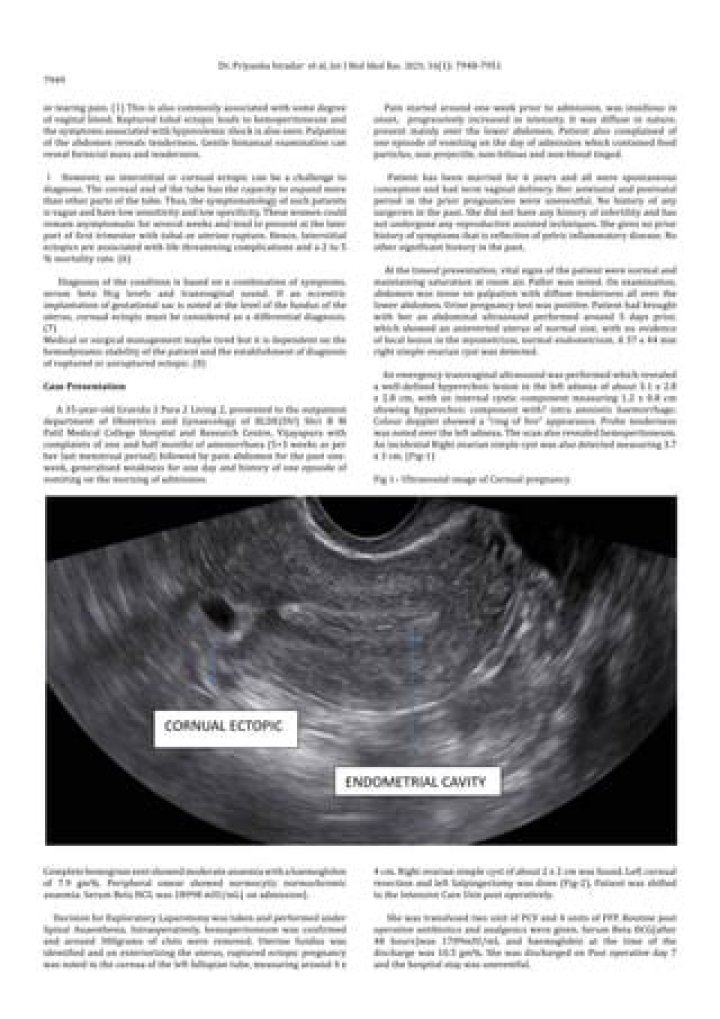

Where is the Cornual region?

Cornual pregnancy The diagnosis is made when only a single interstitial tube is visible on ultrasound. In the majority of cases, a small non-communicating rudimentary horn can be seen adjacent to the medial aspect of the unicornuate uterus14.

Early diagnosis of cornual pregnancy can be done with transvaginal ultrasound. In our case, two abdominal ultrasound scans done one in second and one in third trimester each which failed to diagnose the condition.